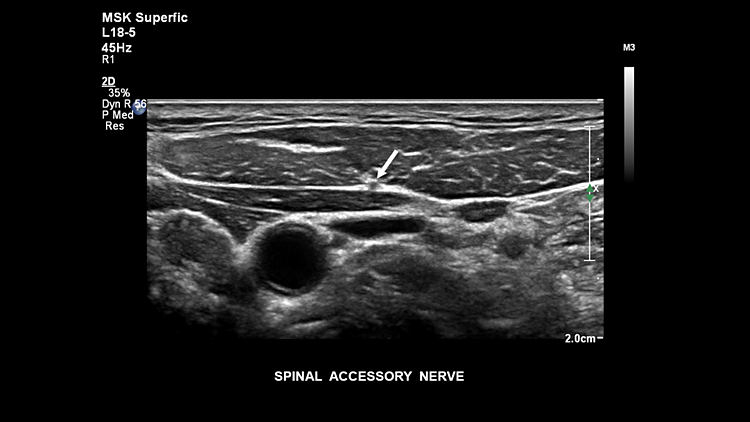

Спинномозговой нерв, L18-5